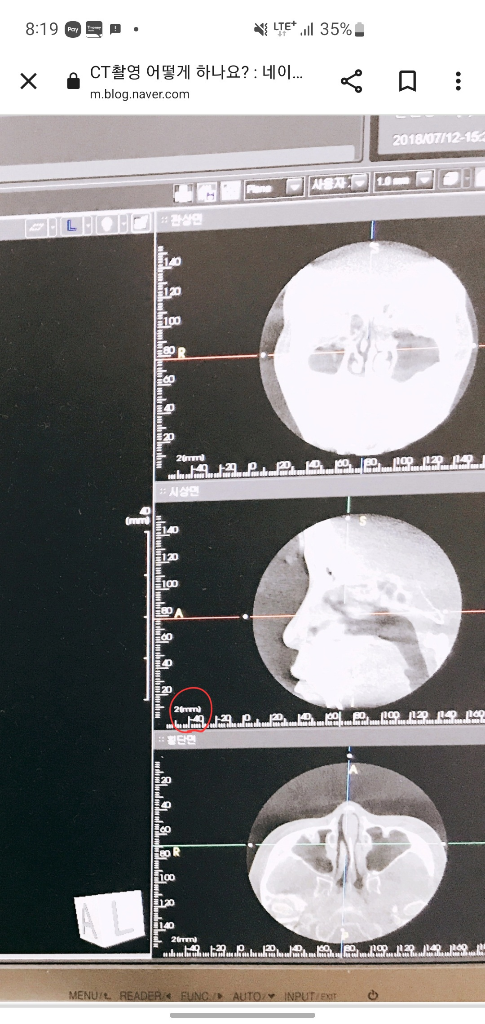

CT 사진이 2mm 간격으로 촬영이 되었다는 의미입니다. 그보다 작은 이물이더라도 촬영된 단면 위에 있으면 관찰이 가능한 것이지, 2mm 크기의 이물질까지 볼 수 있다는 의미는 아닙니다.

2mm 간격으로 촬영된 CT에서는 2mm 이상의 크기를 가진 물질이 촬영될 수 있습니다. 다만 여기서 2mm 이상이라는 것은 가로, 세로, 높이 모두 2mm 이상이 되어야 반드시 영상에 촬영된다는 의미가 됩니다.

2mm단위로 관찰이 가능하지만 이물질의 종류에 따라 방사선에 감지가 되지 않는 이물질이라면 관찰이 되지 않을 수 있습니다.